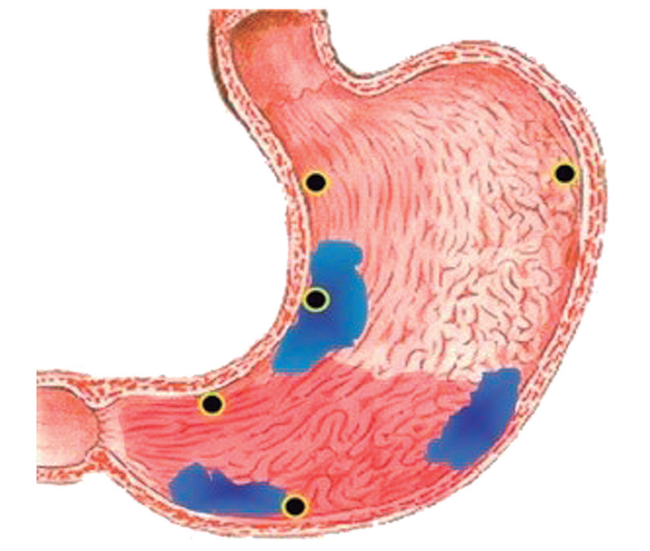

Se han propuesto varias clasificaciones de Gastritis Crónicas, pero para lograr la estandarización en la redacción de informes de patología de biopsias gástricas, los patólogos están siguiendo las recomendaciones de la Clasificación de Sydney modificada (Figura 3).

Se recomiendan 5 biopsias: 2 de Antro a 2-3 cm del píloro (1 biopsia sobre curvatura menor y 1 biopsia sobre curvatura mayor); 2 de Cuerpo a 8 cm del Cardias (1 biopsia sobre curvatura menor y 1 biopsia sobre curvatura mayor) y 1 biopsia de Incisura angularis (Figura 4).